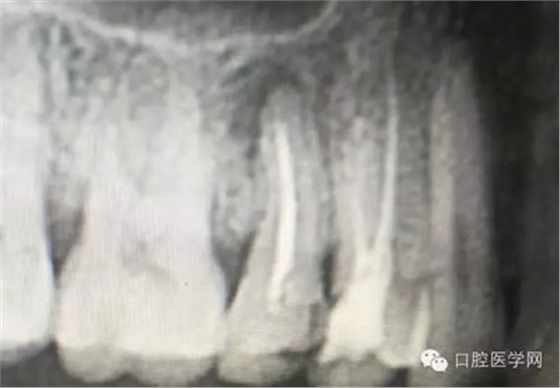

根管再治療是我們比較頭疼的,尤其是那些冠修復(fù)過(guò)的,我們有很多的麻煩需要去溝通,比如可能導(dǎo)致的側(cè)穿、可能沒有看到的腐質(zhì)、可能導(dǎo)致的崩瓷,或者是后期可能出現(xiàn)冠折......這些需要我們和患者好好的溝通。全瓷冠還好些,金屬冠根測(cè)的時(shí)候很是麻煩,總之我們做修復(fù)的時(shí)候不要單純的追求速度,追求效益,適當(dāng)?shù)淖⒁庀挛覀兊幕A(chǔ)治療和設(shè)計(jì)。

深齲或者是齲壞備洞的時(shí)候意外穿髓,我們?cè)趺刺幚砗眯??后期出現(xiàn)的牙髓的癥狀,是我們操作的問(wèn)題?比如細(xì)菌層的存在,我們沒有清理干凈?還是我們窩洞沒有進(jìn)行消毒,或者是隔濕沒有做好導(dǎo)致的粘結(jié)出現(xiàn)問(wèn)題,還是材料充填的時(shí)手法不對(duì),導(dǎo)致的材料收縮過(guò)大,還是我們的光照設(shè)備出現(xiàn)了老化沒有完全達(dá)到想要的固化,還是懸空的釉質(zhì)沒有去除導(dǎo)致的微滲漏的發(fā)生,或者是材料本身對(duì)牙髓產(chǎn)生的刺激,還是材料選擇的問(wèn)題,或者是我們對(duì)材料的性能和說(shuō)明沒有足夠的了解導(dǎo)致的,沒有按照材料的要求去做,還是我們自身對(duì)牙齒情況的判斷出現(xiàn)的問(wèn)題......